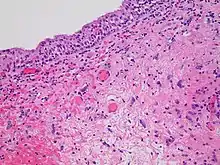

Histopathology of radiation cystitis, including atypical stromal cells ("radiation fibroblasts")

The gastrointestinal tract can be damaged following abdominal and pelvic radiotherapy.[38] Atrophy, fibrosis and vascular changes produce malabsorption, diarrhea, steatorrhea and bleeding with bile acid diarrhea and vitamin B12 malabsorption commonly found due to ileal involvement. Pelvic radiation disease includes radiation proctitis, producing bleeding, diarrhoea and urgency,[39] and can also cause radiation cystitis when the bladder is affected.